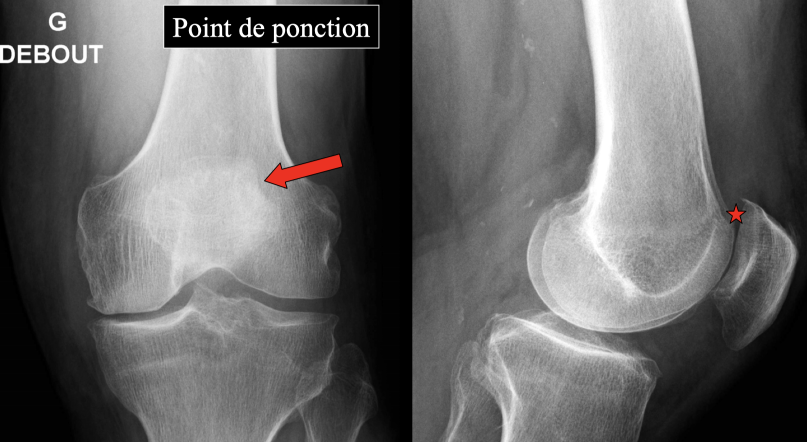

Technique 16cc contraste - 4cc Ropivacaine Luxer latéralement la rotule et piquer latéralement Quantité 15CC Technique Cours